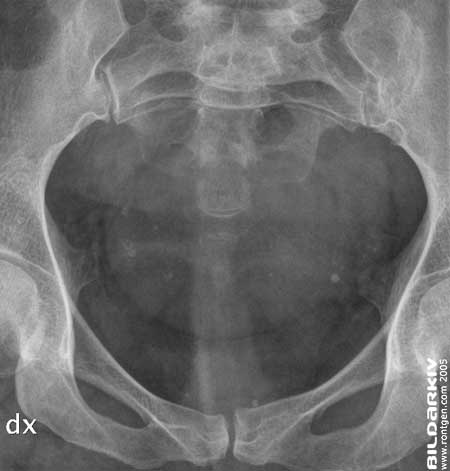

Förbild översikt frontal bild utan intravenös kontrastmedel.